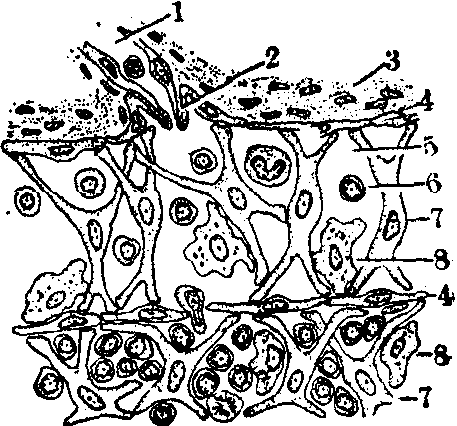

(3)淋巴窦: 位于被膜内面和小梁之间,是宽而扁的窦腔(图1)。窦腔面有内皮细胞,相互以嵌合或重叠的方式连接。在淋巴组织侧,内皮外有薄层网状纤维,再外有网状细胞层,由扁平的网状细胞及其扁平的突起构成,故窦壁由上述三层组成。窦腔内有少量网状细胞支撑,还有许多巨噬细胞附着于网状细胞或内皮细胞的表面(图3)。淋巴流过淋巴窦时,巨噬细胞能随时吞噬和处理其中含有的抗原,并将抗原转到附近的淋巴组织,供淋巴细胞识别和发生相应的免疫应答。

图3 淋巴窦结构(光镜)模式图

1.输入淋巴管 2.瓣膜 3.被膜 4.内皮 5.淋巴窦 6.淋巴细胞 7.成纤维网状细胞 8.巨噬细胞